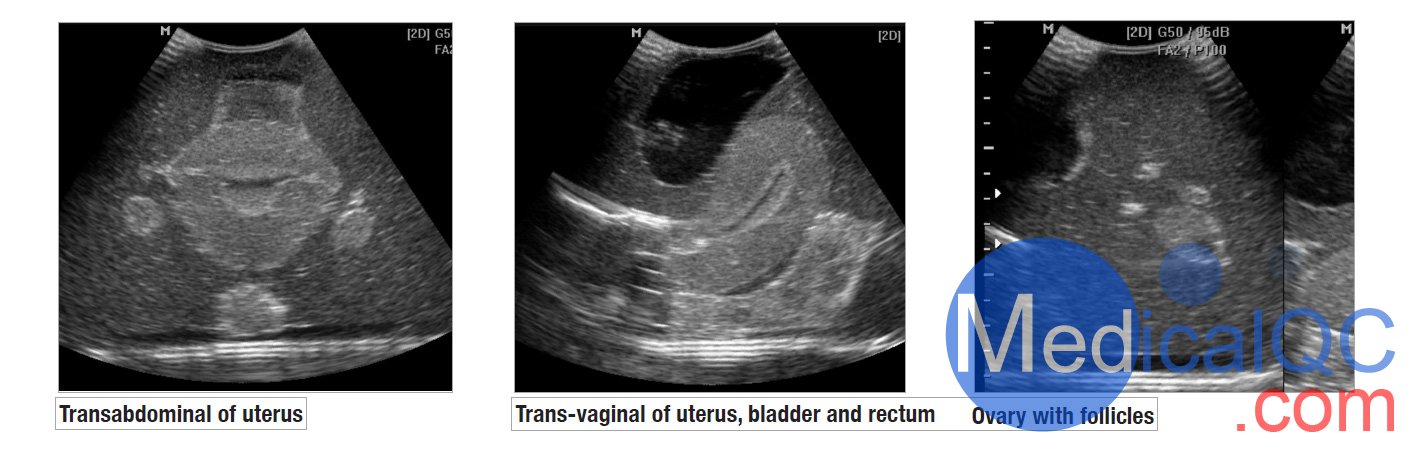

我们的CIrs 404A女性盆腔模体,CIrs 404A超声训练骨盆模体由一个外部女性盆腔模型组成,其中包含用于扫描的子宫、输卵管、卵巢、膀胱和直肠标志。体模具有腹部和阴道扫描通道,允许各种换能器方向。

女性超声训练骨盆为教授和发展超声检查技能和技术以及展示 3D 超声能力创造了一个轻松的学习环境。

腹部和阴道扫描通路

子宫内膜和子宫肌层

有卵泡的卵巢

满膀胱

直肠标志物